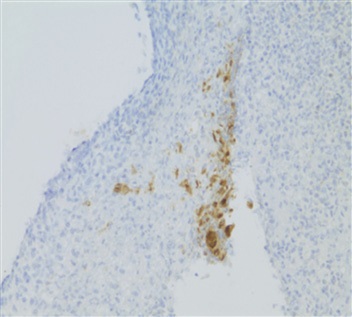

Comprehensive infectious workup was negative except for positive serum and CSF non-treponemal serology. Further testing of the previous right axillary LN specimen with IHC staining revealed Treponema pallidum and a diagnosis of neurosyphilis was confirmed and treatment with 14 days of IV PCN was commenced.

Figure 3: